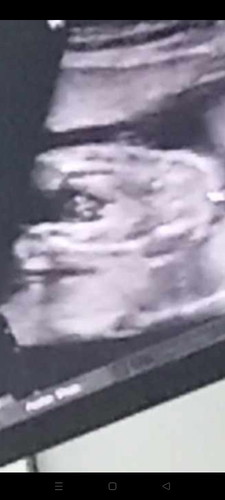

เพศลูกผ่าคลอด

ชายจริงๆใช้มั้ยคะคนเเรกชายคนที่2อยากได้ผู้หญิงบ้างเเล้วเเม่ผ่าคลอดท้อง2กันตอนกี่วิคกันบ้างคะ